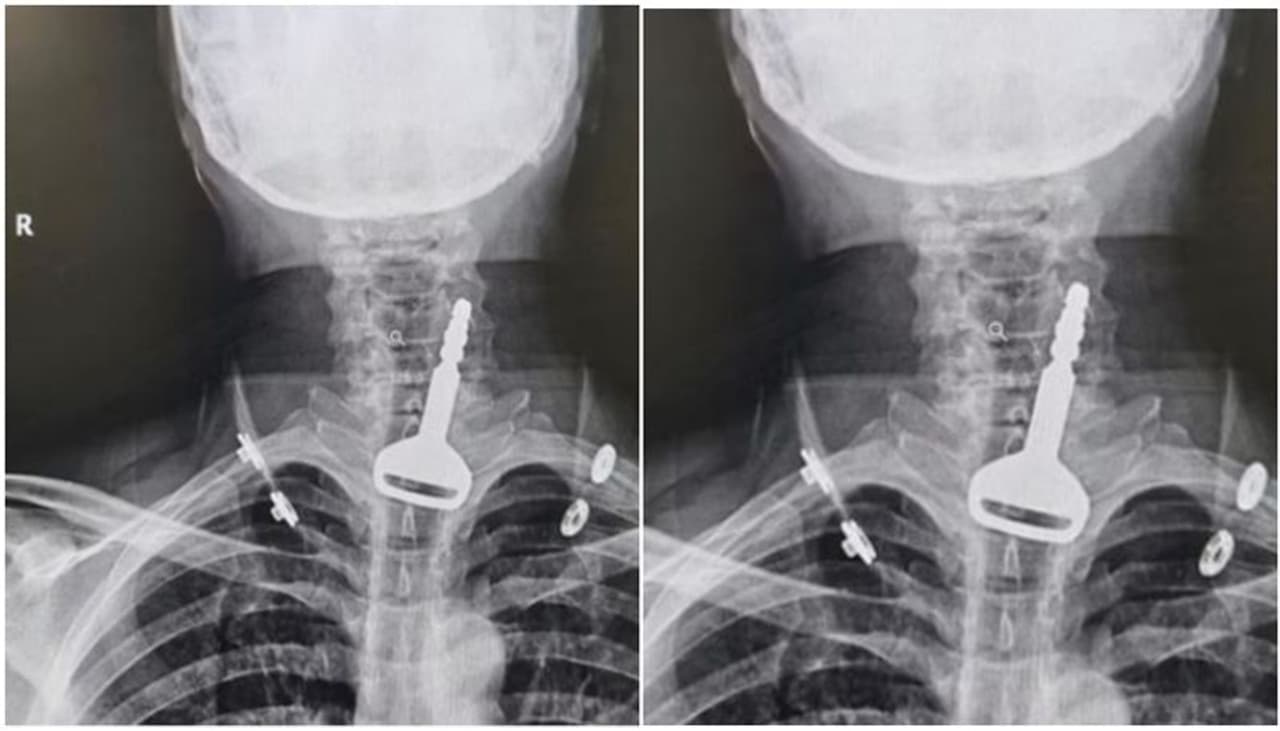

റിയാദ്: കടുത്ത ശ്വാസംമുട്ടലുമായി ആശുപത്രിയിലെത്തിയ 49 കാരനെ എക്സ് റേ പരിശോധനയ്ക്ക് വിധേയനാക്കിയപ്പോള് കണ്ടത് കാറിന്റെ താക്കോല്. ശ്വാസനാളത്തില് കുടുങ്ങിയ നിലയിലാണ് താക്കോല് കണ്ടത്. സൗദി അറബ്യേയിലാണ് സംഭവം ഉണ്ടായത്.

ശ്വാസമെടുക്കാന് പ്രയാസം നേരിട്ടതോടെയാണ് 49 കാരന് സൗദിയിലെ അല് ഖുന്ഫുധാ ഗവര്ണറേറ്റിലെ ആശുപത്രിയിലെത്തിയത്. തുടര്ന്ന് ഡോക്ടര്മാര് നടത്തിയ എക്സ് റേ പരിശോധനയിലാണ് ഞെട്ടിക്കുന്ന വിവരം അറിഞ്ഞത്. ഇദ്ദേഹത്തിന്റെ ശ്വാസനാളത്തില് കാറിന്റെ താക്കോല് കുടുങ്ങിയതായി കണ്ടെത്തുകയായിരുന്നു.

താക്കോല് വായിലിട്ട് വെറുതെ കളിച്ചുകൊണ്ടിരുന്നപ്പോള് അറിയാതെ വിഴുങ്ങിപ്പോയതാണെന്ന് 49കാരന് പിന്നീട് ഡോക്ടര്മാരോട് പറഞ്ഞു. ഹൃദ്രോഗി കൂടിയായത് കൊണ്ട് ഇദ്ദേഹത്തിന്റെ ശ്വാസനാളത്തില് നിന്നും താക്കോലെടുക്കുന്നത് സങ്കീര്ണമായി. പിന്നീട് എന്ഡോസ്കോപ്പി നടത്തി. ലാപ്രോസ്കോപ്പി വഴി താക്കോല് അപകടമൊന്നും കൂടാതെ പുറത്തെടുക്കുകയായിരുന്നു. വിജയകരമായി താക്കോല് പുറത്തെടുക്കാനായി. ആരോഗ്യനില സാധാരണനിലയിലാകുന്നത് വരെ ആശുപത്രിയില് നിരീക്ഷണത്തില് കഴിയുകയാണ് 49കാരന്.